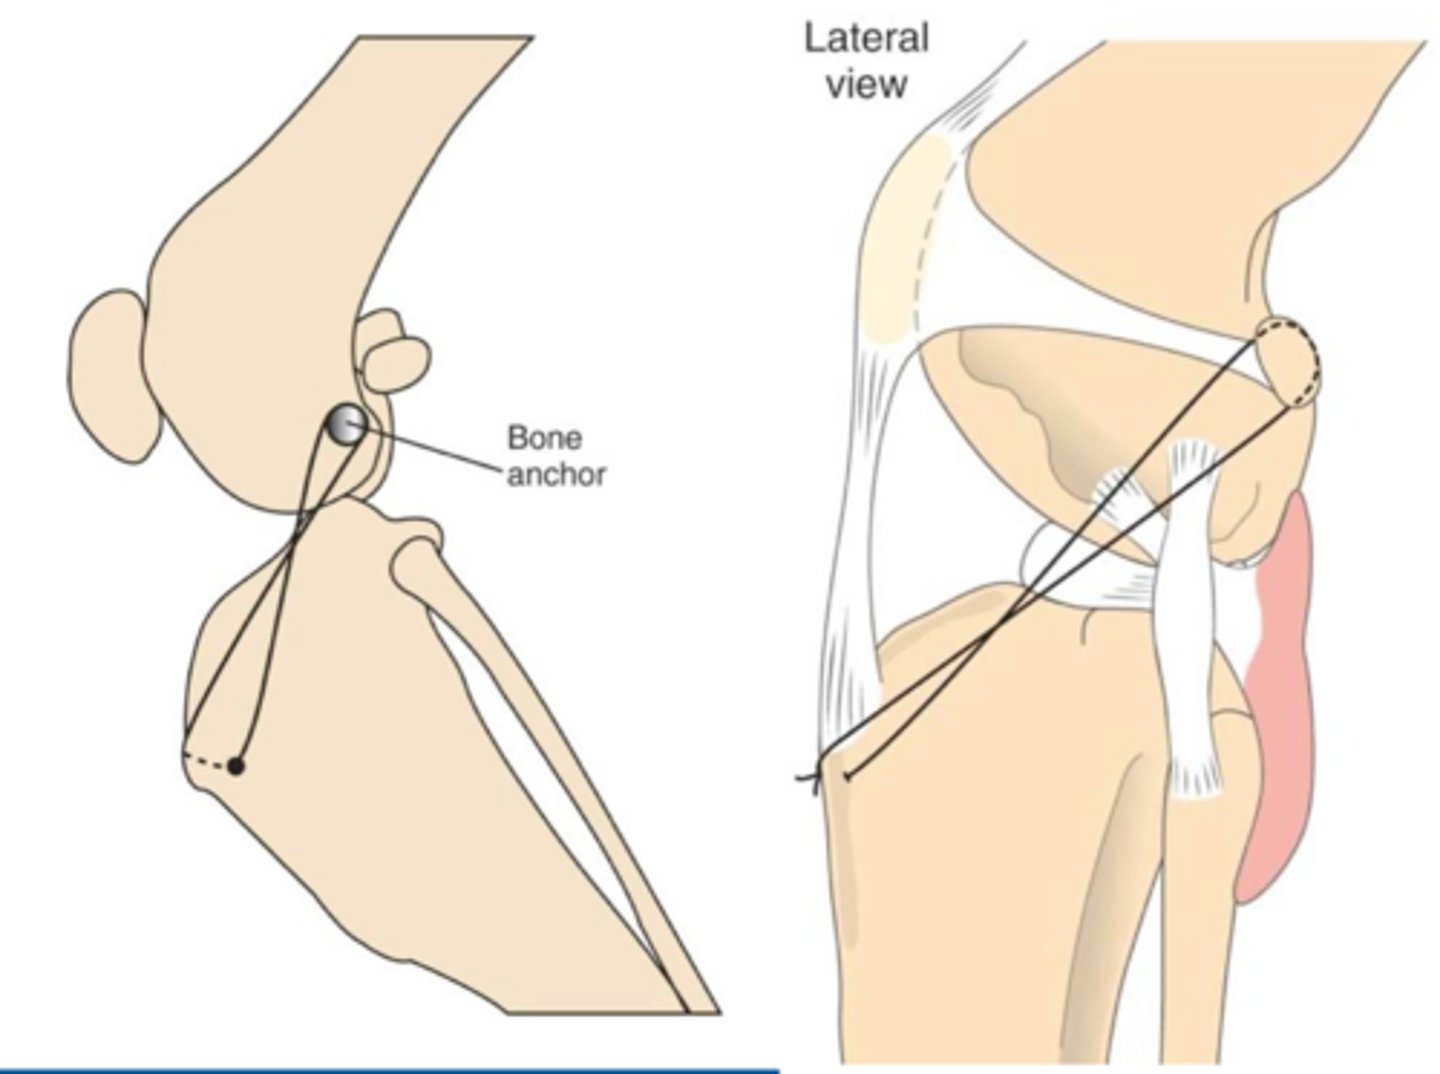

placement of suture outside of joint

what is involved in extracapsular reconstruction of CCL rupture

1. bone anchors

2. bone tunnels

what are some methods to secure extracapsular sutures

1. monofilament nylon or fishing/leader wire

2. manufactured orthopedic wire

3. braided orthopedic wire

what materials are often used in extracapsular sutures

tightrope stabilization

what procedure is shown here